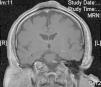

Varón de 62 años sin antecedentes de interés, salvo por la realización desde los 15 años de edad de yoga en posición invertida durante media hora varias veces al día. Consultó por la aparición hacía más de 20 años de una lesión sobreelevada, persistente, en la región interparietal, asintomática, con crecimiento inicial durante los primeros años y estabilización posterior. Esta lesión se ulceraba y sobreinfectaba ocasionalmente, resolviéndose de forma espontánea o con tratamiento antibiótico en unos 10 días. A la exploración física presentaba en la región interparietal una lesión tuberosa de aproximadamente 10cm de longitud anteroposterior por 6cm de ancho, de morfología ovalada, de consistencia dura, con una superficie erosionada en la región central (figs. 1A y B). En la analítica no se encontraron alteraciones significativas. Una radiografía de cráneo mostró un aumento de partes blandas en la región parietal, con reacción perióstica asociada, por lo que se realizó una TAC cerebral con contraste que evidenció una masa de partes blandas extracraneales en la región de la convexidad frontal alta en la línea media, con discreta reacción perióstica subyacente, sin clara afectación de la tabla externa del diploe, compatible con proceso reactivo. En la biopsia cutánea realizada se observó en la epidermis una marcada hiperqueratosis de tipo ortoqueratósico y ligera acantosis. En la dermis presentaba fibrosis focal con proliferación de pequeños vasos, densos infiltrados perivasculares linfocitarios y aislados siderófagos (figs. 2A y B). En la resonancia magnética cerebral era evidente un engrosamiento de partes blandas extracraneales a nivel de las suturas coronal y sagital y de la tabla externa que mostraba hipointensidad en todas las secuencias en relación con reacción ósea esclerosa, hallazgos compatibles con cambios fibróticos afectando a las partes blandas extracraneales y reacción esclerótica ósea de la cortical del hueso subyacente (fig. 3).